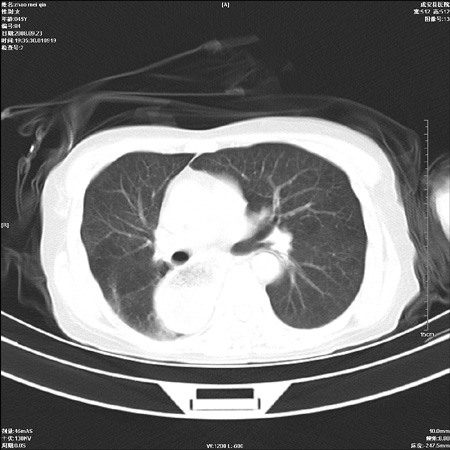

标题: CT15861:女 60 外伤后1小时 胸疼 [打印本页]

标题: CT15861:女 60 外伤后1小时 胸疼

外伤后1小时 胸疼 是外伤后引起的吗?

食道扩张,有无手术史?

考虑术后改变(胸腔胃),建议询问病史.

食道扩张明显下端逐渐变窄,大量食物存留,象贲门失迟缓症。